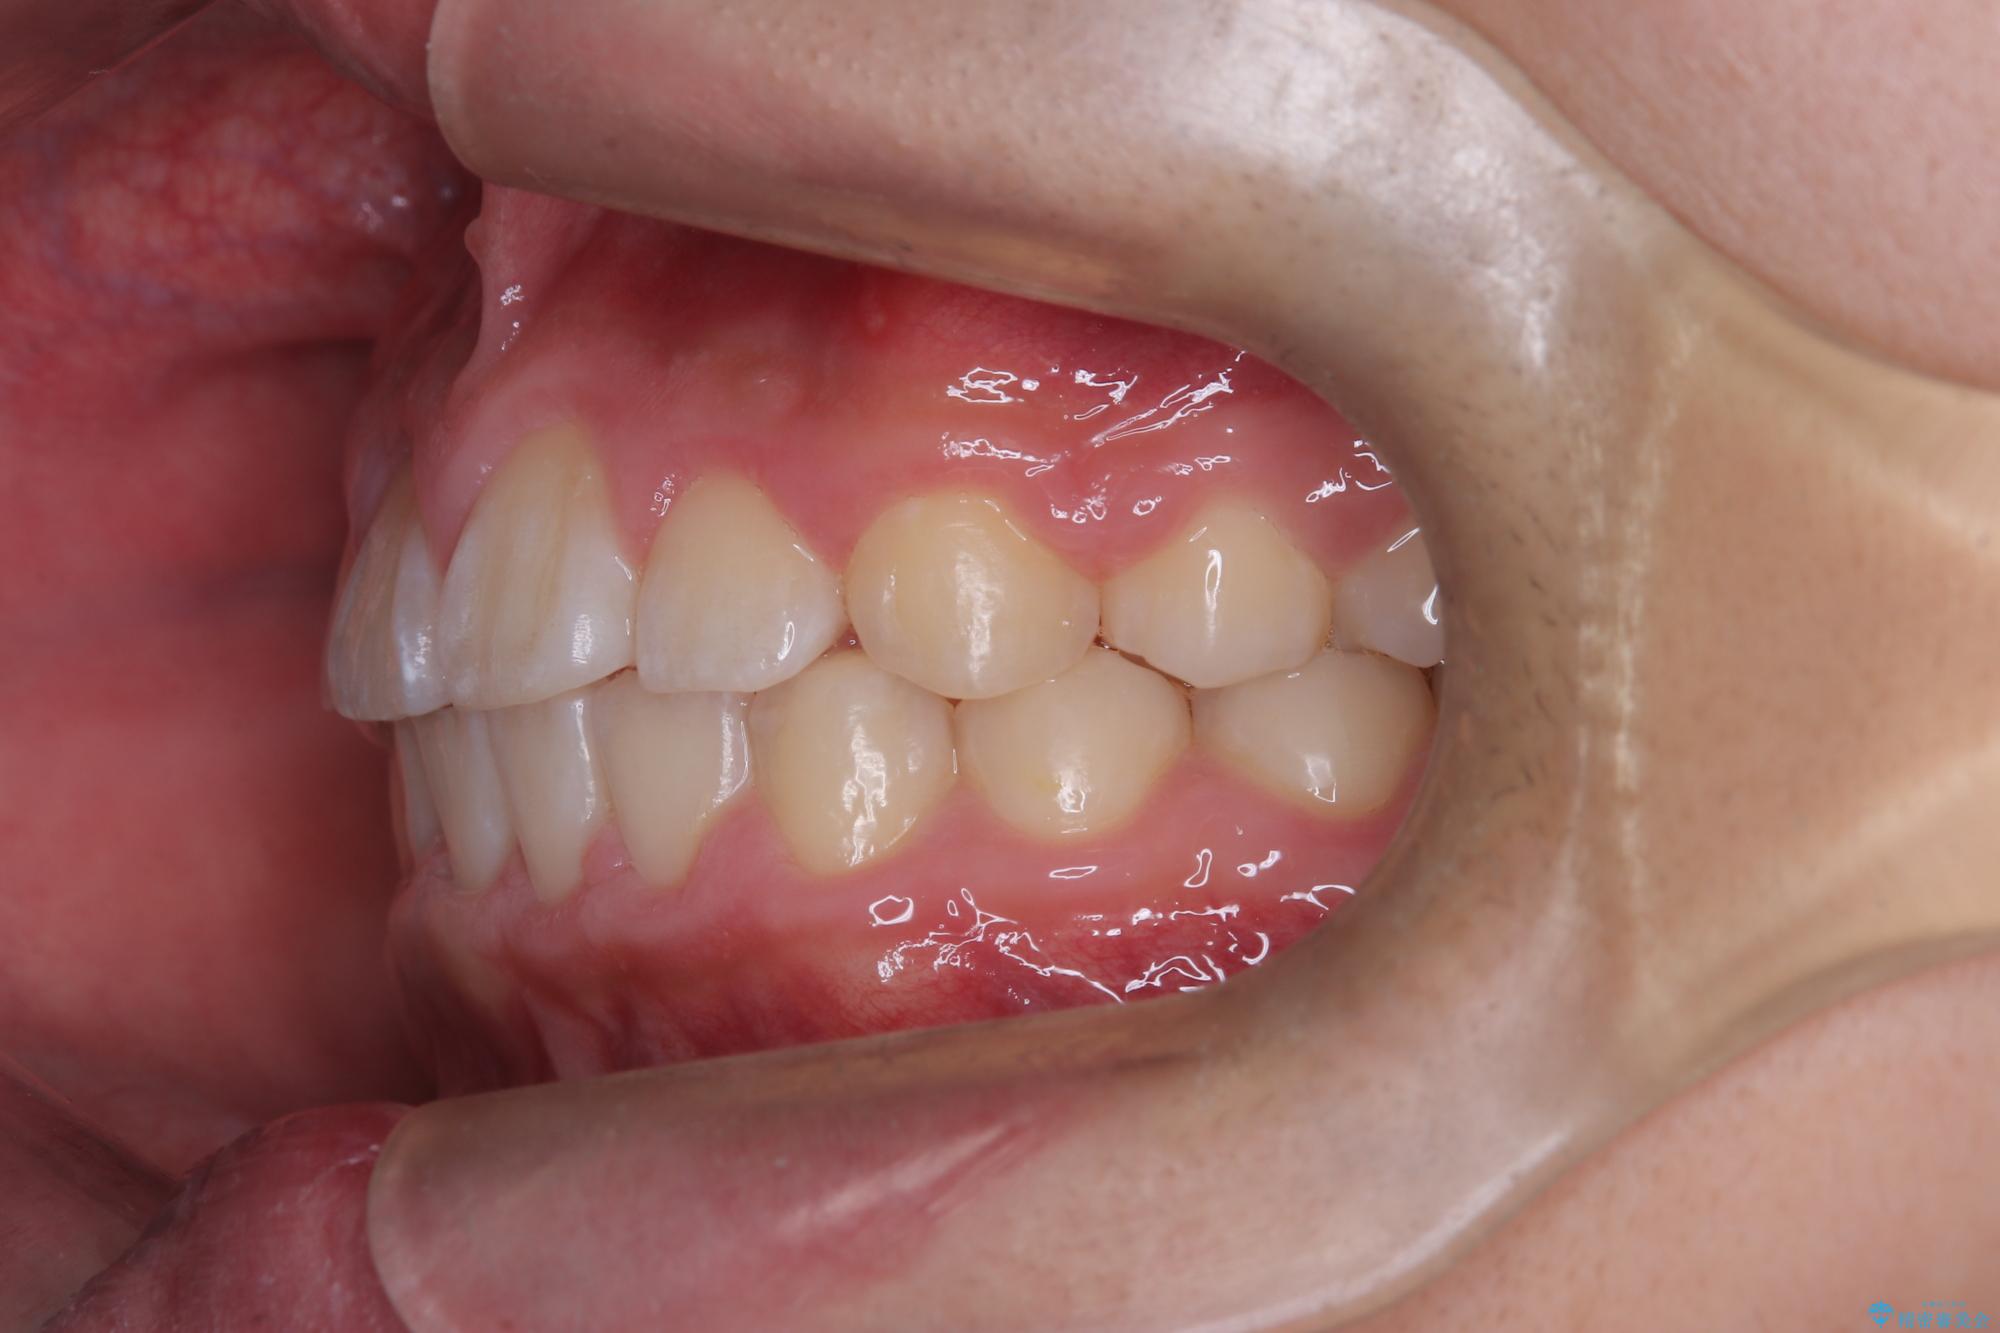

八重歯・歯並びのデコボコとディープバイトを改善した抜歯ワイヤー矯正症例

- 八重歯と咬み合わせを治したいを主訴にご来院された患者様です。

矯正の精密検査の結果上顎左右4番の計2本を抜歯し、審美性に配慮したワイヤー矯正装置(審美装置)を用いて治療を行いました。

八重歯などの歯列のデコボコが綺麗に改善され、患者様にも大変喜んでいただけました。また、咬み合わせが深い「ディープバイト」も併せて改善し、見た目だけでなく機能面でもバランスの取れた咬合を獲得しています。